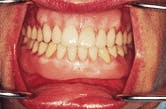

Figure 1-The patient has had four implants placed in the mandibular anterior segment. The denture is unsatisfactory to the patient in the three critical areas of esthetics, comfort and function.

Figure 1